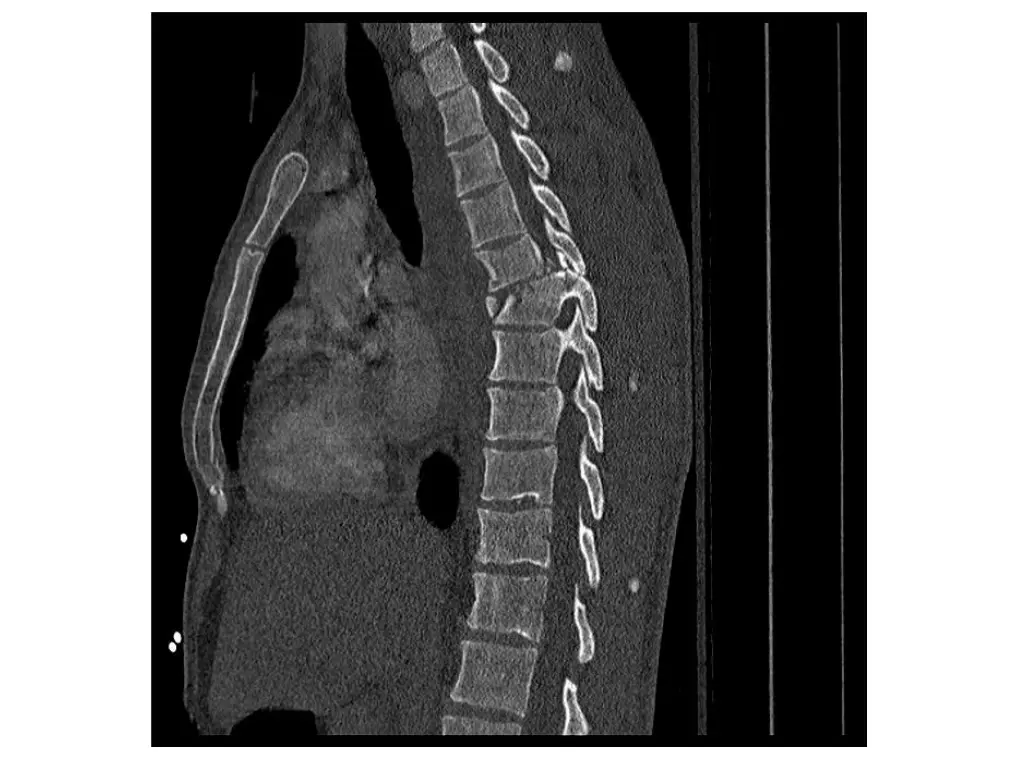

Imaging (Case 1) Midsagittal CT scan Parasagittal CT scan Axial CT scan Midsagittal STIR MRI scan

Imaging (Case 2) Lateral XR Midsagittal CT scan Parasagittal CT scan Axial CT scan

Imaging (Case 3) Lateral XR Midsagittal CT scan Parasagittal CT scan